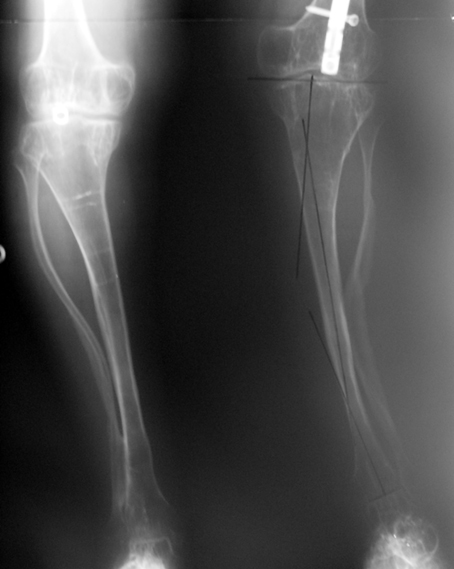

Case 3